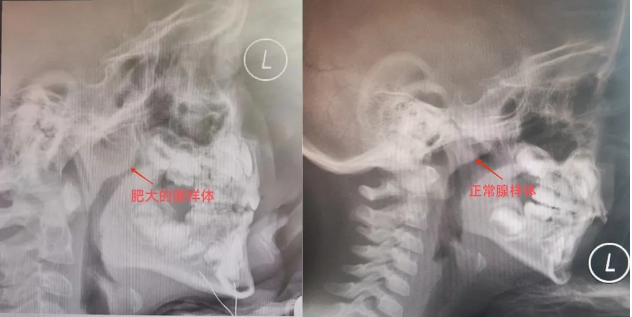

※洋洋的腺樣體并沒有復(fù)發(fā)肥大跡象

洋洋辦理入院后在全麻下接受了腭咽成形術(shù),術(shù)中切除了雙側(cè)扁桃體,所切除的扁桃體呈現(xiàn)包埋型,即大部分隱藏于扁桃體窩內(nèi),所暴露在外的部分于查體時見僅為1度大小,但實(shí)則“內(nèi)有乾坤”,術(shù)中同期將兩側(cè)扁桃體窩內(nèi)的黏膜進(jìn)行了對位縫合,進(jìn)一步擴(kuò)大了咽腔的空間,手術(shù)順利結(jié)束,洋洋安返病房。